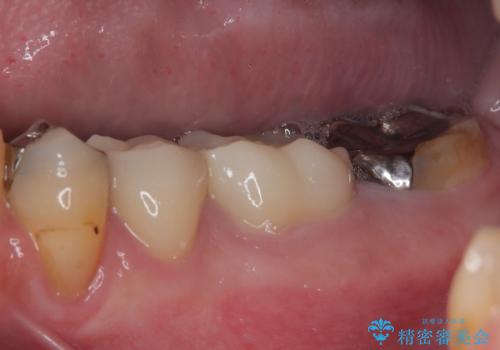

根管治療を実施した後に、フルジルコニアクラウンにて補綴することとしました。

症状のあった歯に対しても根管治療を行い、同様に補綴治療を行いました。